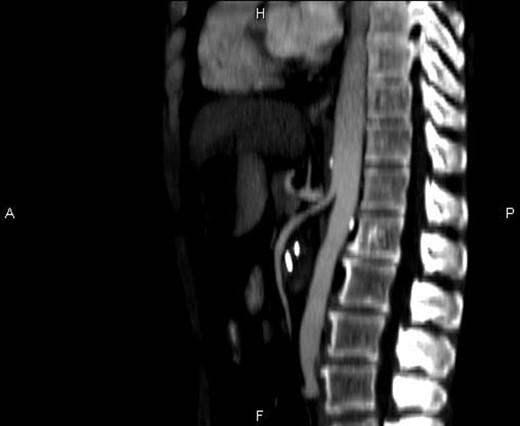

Computerized tomography (CT) scan of the upper and lower abdomen excluded the possibility of a tumor or an annular pancreas to be the cause of the compression of the duodenum. The subsequent CT scan showed an acute angle of 15° (Figs. 2 and 3) between the superior mesenteric artery and the aorta.

Sagittal CT image showing the entrapment of the duodenum between the aorta and the SMA.